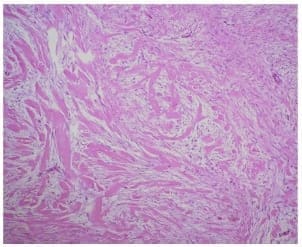

El examen microscópico informó la presencia de proliferación mesenquimática entremezclada con haces voluminosos de colágeno grueso, compuesta por células dispuestas en haces fusiformes, de núcleos estrellados y con recuento mitótico mínimo o ausente. Presentaba vascularización prominente sin necrosis ni hemorragia, hallazgos compatibles con un tumor desmoide (Figura 4).

Figura 4. Microfotografía que muestra la proliferación mesenquimática entremezclada con gruesos haces de colágeno. Hematoxilina & eosina. 10x.